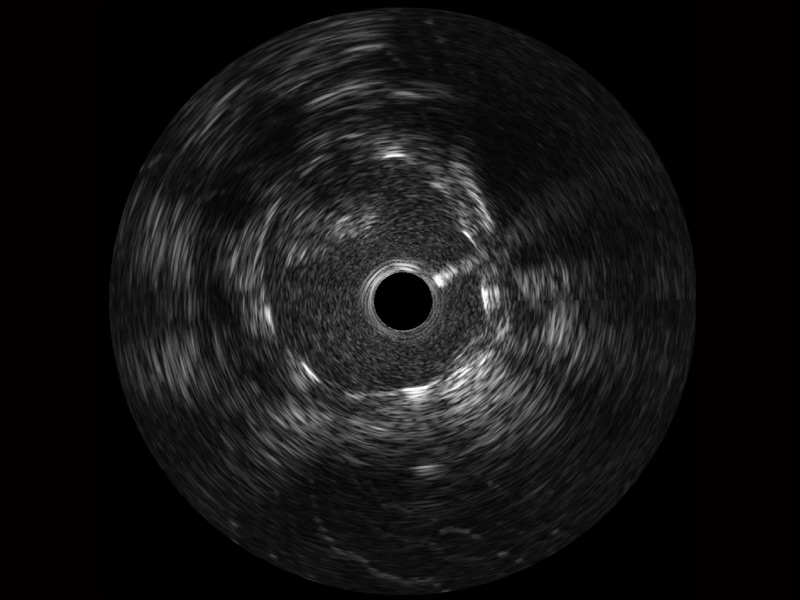

16877太阳集团宽频IVUS图像

传统IVUS图像

对比传统IVUS导管成像,16877太阳集团宽频IVUS图像的近场支架梁显影更细腻,远场中膜外血管仍清晰可辨,兼顾远中近,兼顾分辨力与穿透深度